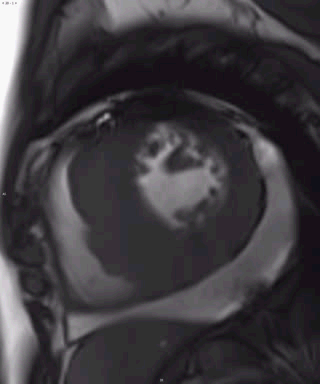

病例三

● 男,20

● 无高血压病史

征象:

左心室心肌不对称性肥厚,间隔壁为著

舒张功能减低

收缩期二尖瓣前叶前移,静息状态下左心室流出道梗阻

收缩期见二尖瓣区向心房侧束状低信号

心包内见液性信号

LGE:左心室心肌中层条片状高信号

非对称性梗阻性肥厚型心肌病

间隔壁最厚室壁厚度>30mm

左心室心肌中层弥漫心肌纤维化

左房增大,二尖瓣关闭不全

心包积液